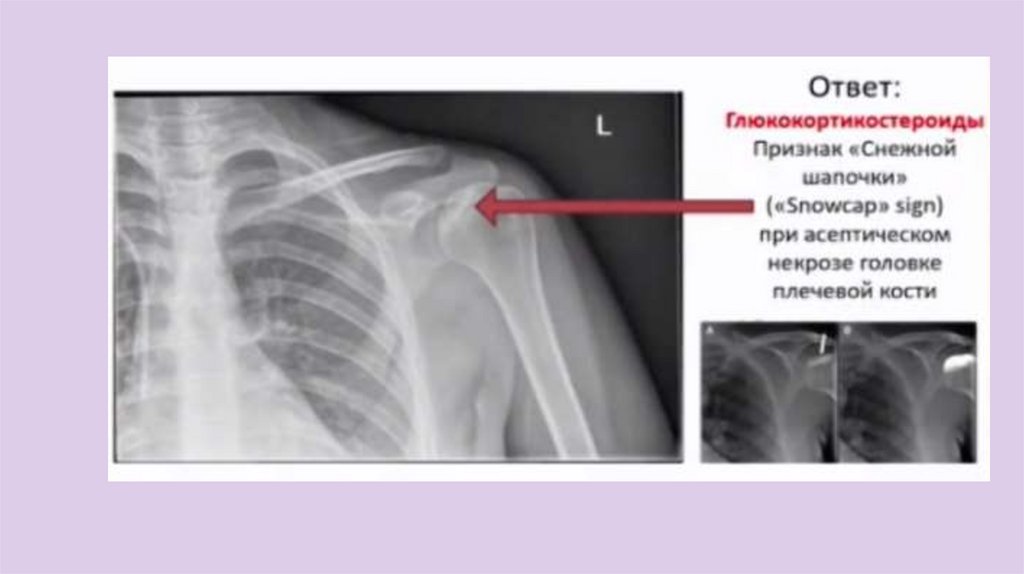

Догадавшись, в чем тут проблема, назовите

группу лекарственных препаратов, которые

чаще всего приводят к данной патологии

19.